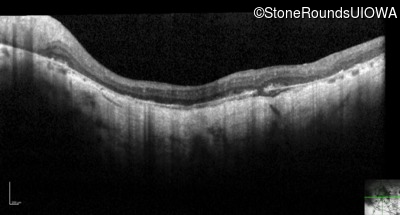

Optical Coherence Tomography - Right - 2/700 sc

Exemplar / OCT Stack